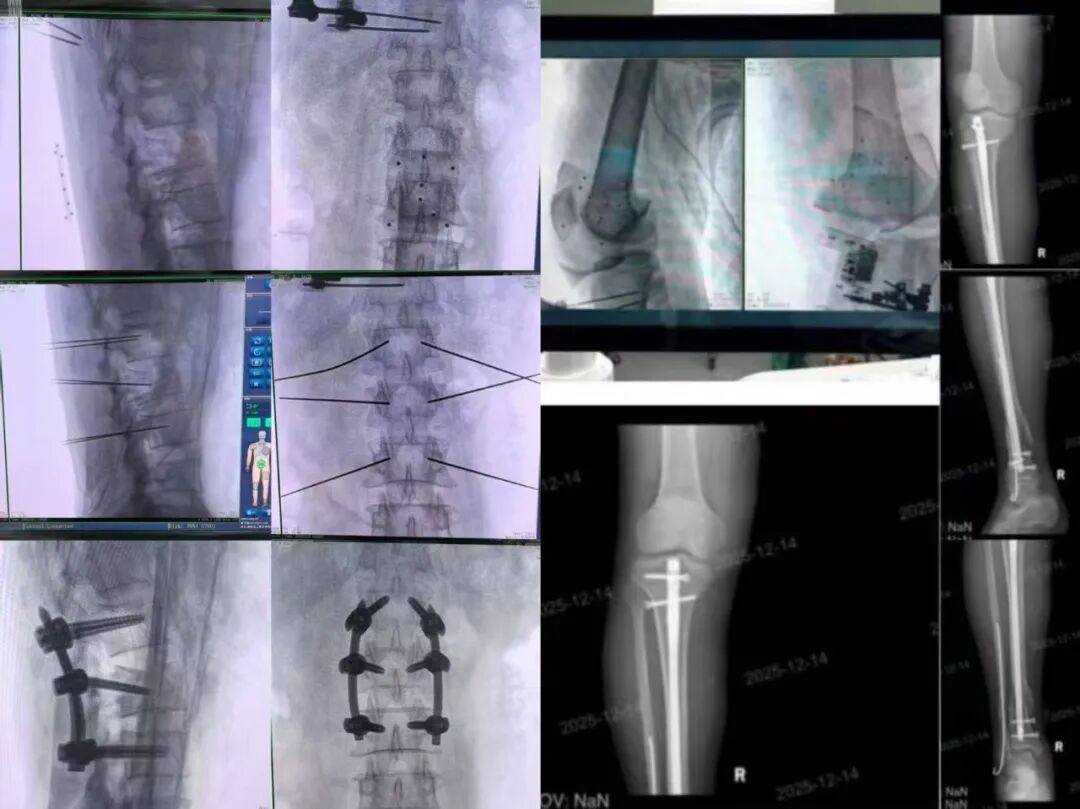

前沿科技,边疆落地。近日,新疆生产建设兵团医院骨科成功引进并应用天玑思睿骨科手术机器人,在脊柱与创伤领域连续完成多例高精度机器人辅助手术。让高端医疗科技突破地域限制,助力提升区域诊疗水平,是天智航始终如一的追求。

科技赋能手术,天玑思睿三大核心优势突显 1 三维智能规划,全流程可视化 SUMMARY 基于术中三维影像,快速重建患者骨骼立体模型,主刀医生在虚拟三维空间中规划螺钉最佳植入路径,一次性完成全程规划,大幅提升手术效率,降低术中调整风险。

天玑思睿高精度的光学导航系统,配合360°主动跟踪器,实现了对患者和机械臂位置的实时追踪。此外,搭载手术器械的高灵敏机械臂,能够将规划路径转化为亚毫米级(<1mm)的精准操作,消除了人手不可避免的细微震颤,确保每一颗螺钉均沿“安全通道”植入

机器人辅助实现了精准植入,避免传统手术中对健康肌肉组织的大范围剥离,减少术中出血与组织损伤,加速患者康复,缩短住院时间,真正体现“以患者为中心”的精准医疗理念。